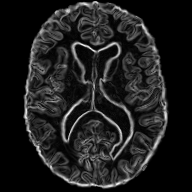

Diffeomorphic deformable multi-modal image registration is a challenging task which aims to bring images acquired by different modalities to the same coordinate space and at the same time to preserve the topology and the invertibility of the transformation. Recent research has focused on leveraging deep learning approaches for this task as these have been shown to achieve competitive registration accuracy while being computationally more efficient than traditional iterative registration methods. In this work, we propose a simple yet effective unsupervised deep learning-based multi-modal image registration approach that benefits from auxiliary information coming from the gradient magnitude of the image, i.e. the image edges, during the training. The intuition behind this is that image locations with a strong gradient are assumed to denote a transition of tissues, which are locations of high information value able to act as a geometry constraint. The task is similar to using segmentation maps to drive the training, but the edge maps are easier and faster to acquire and do not require annotations. We evaluate our approach in the context of registering multi-modal (T1w to T2w) magnetic resonance (MR) brain images of different subjects using three different loss functions that are said to assist multi-modal registration, showing that in all cases the auxiliary information leads to better results without compromising the runtime.

In this paper, we propose a novel unsupervised multi-modal image registration approach to tackle the problem of registering images of different subjects (inter-subject) acquired by two different imaging modalities (T1w, T2w MR images). We are integrating ideas from the work of Pluim et al. [10] that combines mutual information with a term based on the magnitude and direction of the image gradients to rigidly register 3D MR, CT and PET images, the work of Qin et al. [11] that uses segmentation maps as auxiliary information to guide the task of motion estimation and the work of Zhe Xu at al. [12] that performs unsupervised multimodal CT-MR image registration leveraging the deformation fields estimated from a branch aiming to align the original fixed and moving images and a branch aiming to align the corresponding gradient intensity maps.

Similarly, we propose to make use of the edge maps extracted the images, as a complementary signal, to aid the training of registration network. The main assumption is that since the anatomy depicted by the two modalities is very similar, the edge maps can serve as a geometrical constraint. At the same time,

the edges are less \saymodality dependent, a property that is very useful in the case of multi-modal registration due to the fact that we do not have to deal with the complicated intensity relationship between the modalities. This simple, yet, effective technique shows that the edge signal can be beneficial for multi-modal image registration.

2.1 Edge Maps

As stated above, the edge maps extracted from multi-modal images can be a useful auxiliary information to guide multi-modal image registration. Specifically, the edge map of a 2D (but easily extensible to 3D) image can be easily obtained by calculating the central differences between adjacent pixels.

We decided to only use the gradient magnitude because it is sufficient to depict the underlying geometry and discard the information relating to the edge direction. The part of the network that handles the edge maps is more sensitive in capturing the structural dependencies between the two images, rather than the complex intensity relationships, and hence serves as a spatial constraint assisting the task of image registration. In practice, the edge maps are given as input to an encoder which adopts the same architecture as the one that handles the images.

We evaluate our work on the task of inter-subject brain MRI registration on T1w-T2w images. For this purpose, we decided to use the Cambridge Centre for Ageing and Neuroscience (CamCAN) dataset [20], [21]. The dataset consist T1w and T2w MR 3D volumetric images of 310 subjects, with isotropic spatial resolution. In our work we only use 2D slicse of the volumetric image cropped to the size of . Although this work could directly be transferred in 3D, we use 2D images as a proof-of-concept, due to the large computational requirements when using 3D images. After affine alignment to a common MNI space using ANTs [22], the images are skull-stripped using ROBEX [23] and bias-field corrected using the N4 algorithm in SimpleITK [24]. For evaluation, we also acquired the segmentation of 138 cortical and sub-cortical structures (grouped into 5 groups) automatically using MALPEM [25].